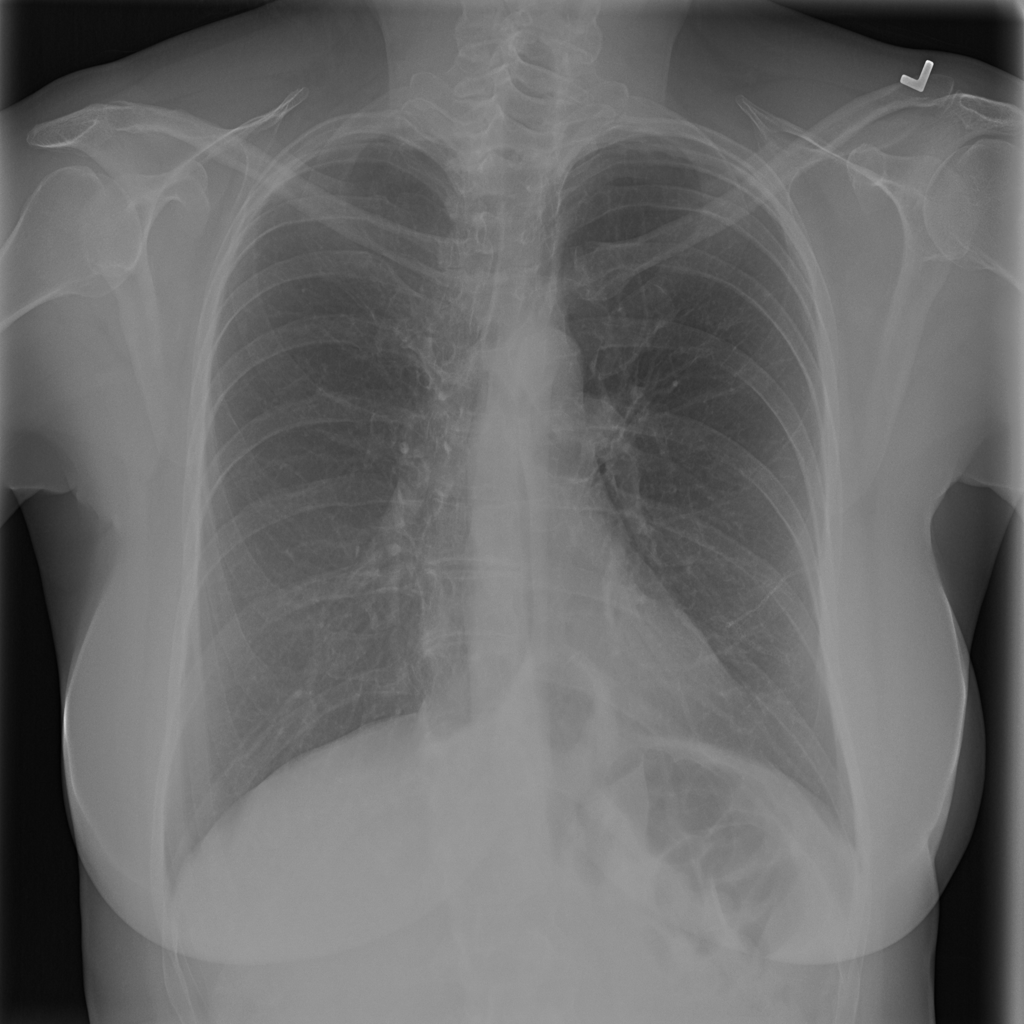

Showing up to 90 reference images for Hernia.

PAT-0ABD · IMG-000Hernia

PAT-0ABD · IMG-000

PA